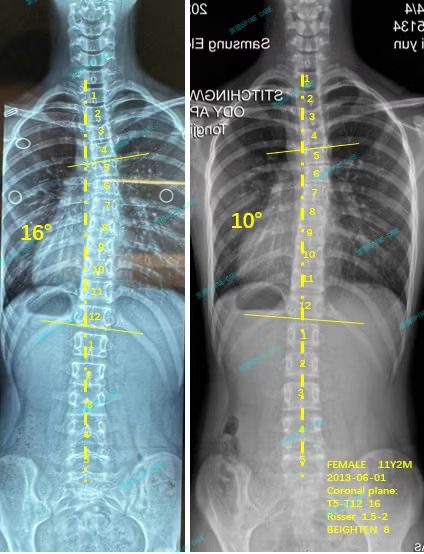

案例主人:蕴蕴 发现侧弯年龄:12岁 侧弯情况:Cobb角度16度

就这样,到现在我已经坚持锻炼将近一年的时间了。最近再次去拍片检查,结果显示我的胸弯从之前的16度成功降低到了10度,这真的是一个超级好的消息,让我和爸爸妈妈都感到无比开心。而且呀,不仅我的胸弯度数降低了,我的身体也比以前直了很多很多,现在几乎都看不出来我曾经有脊柱侧弯的样子啦!

In this way, I have been exercising for nearly a year now. Recently, I went for an X-ray examination again, and the results showed that my chest curvature had been successfully reduced from the previous 16 degrees to 10 degrees. This was really super good news, which made my parents and I feel extremely happy. Moreover, not only has my chest curvature decreased, but my body is also much, much straighter than before. Now it is almost impossible to see that I once had scoliosis!